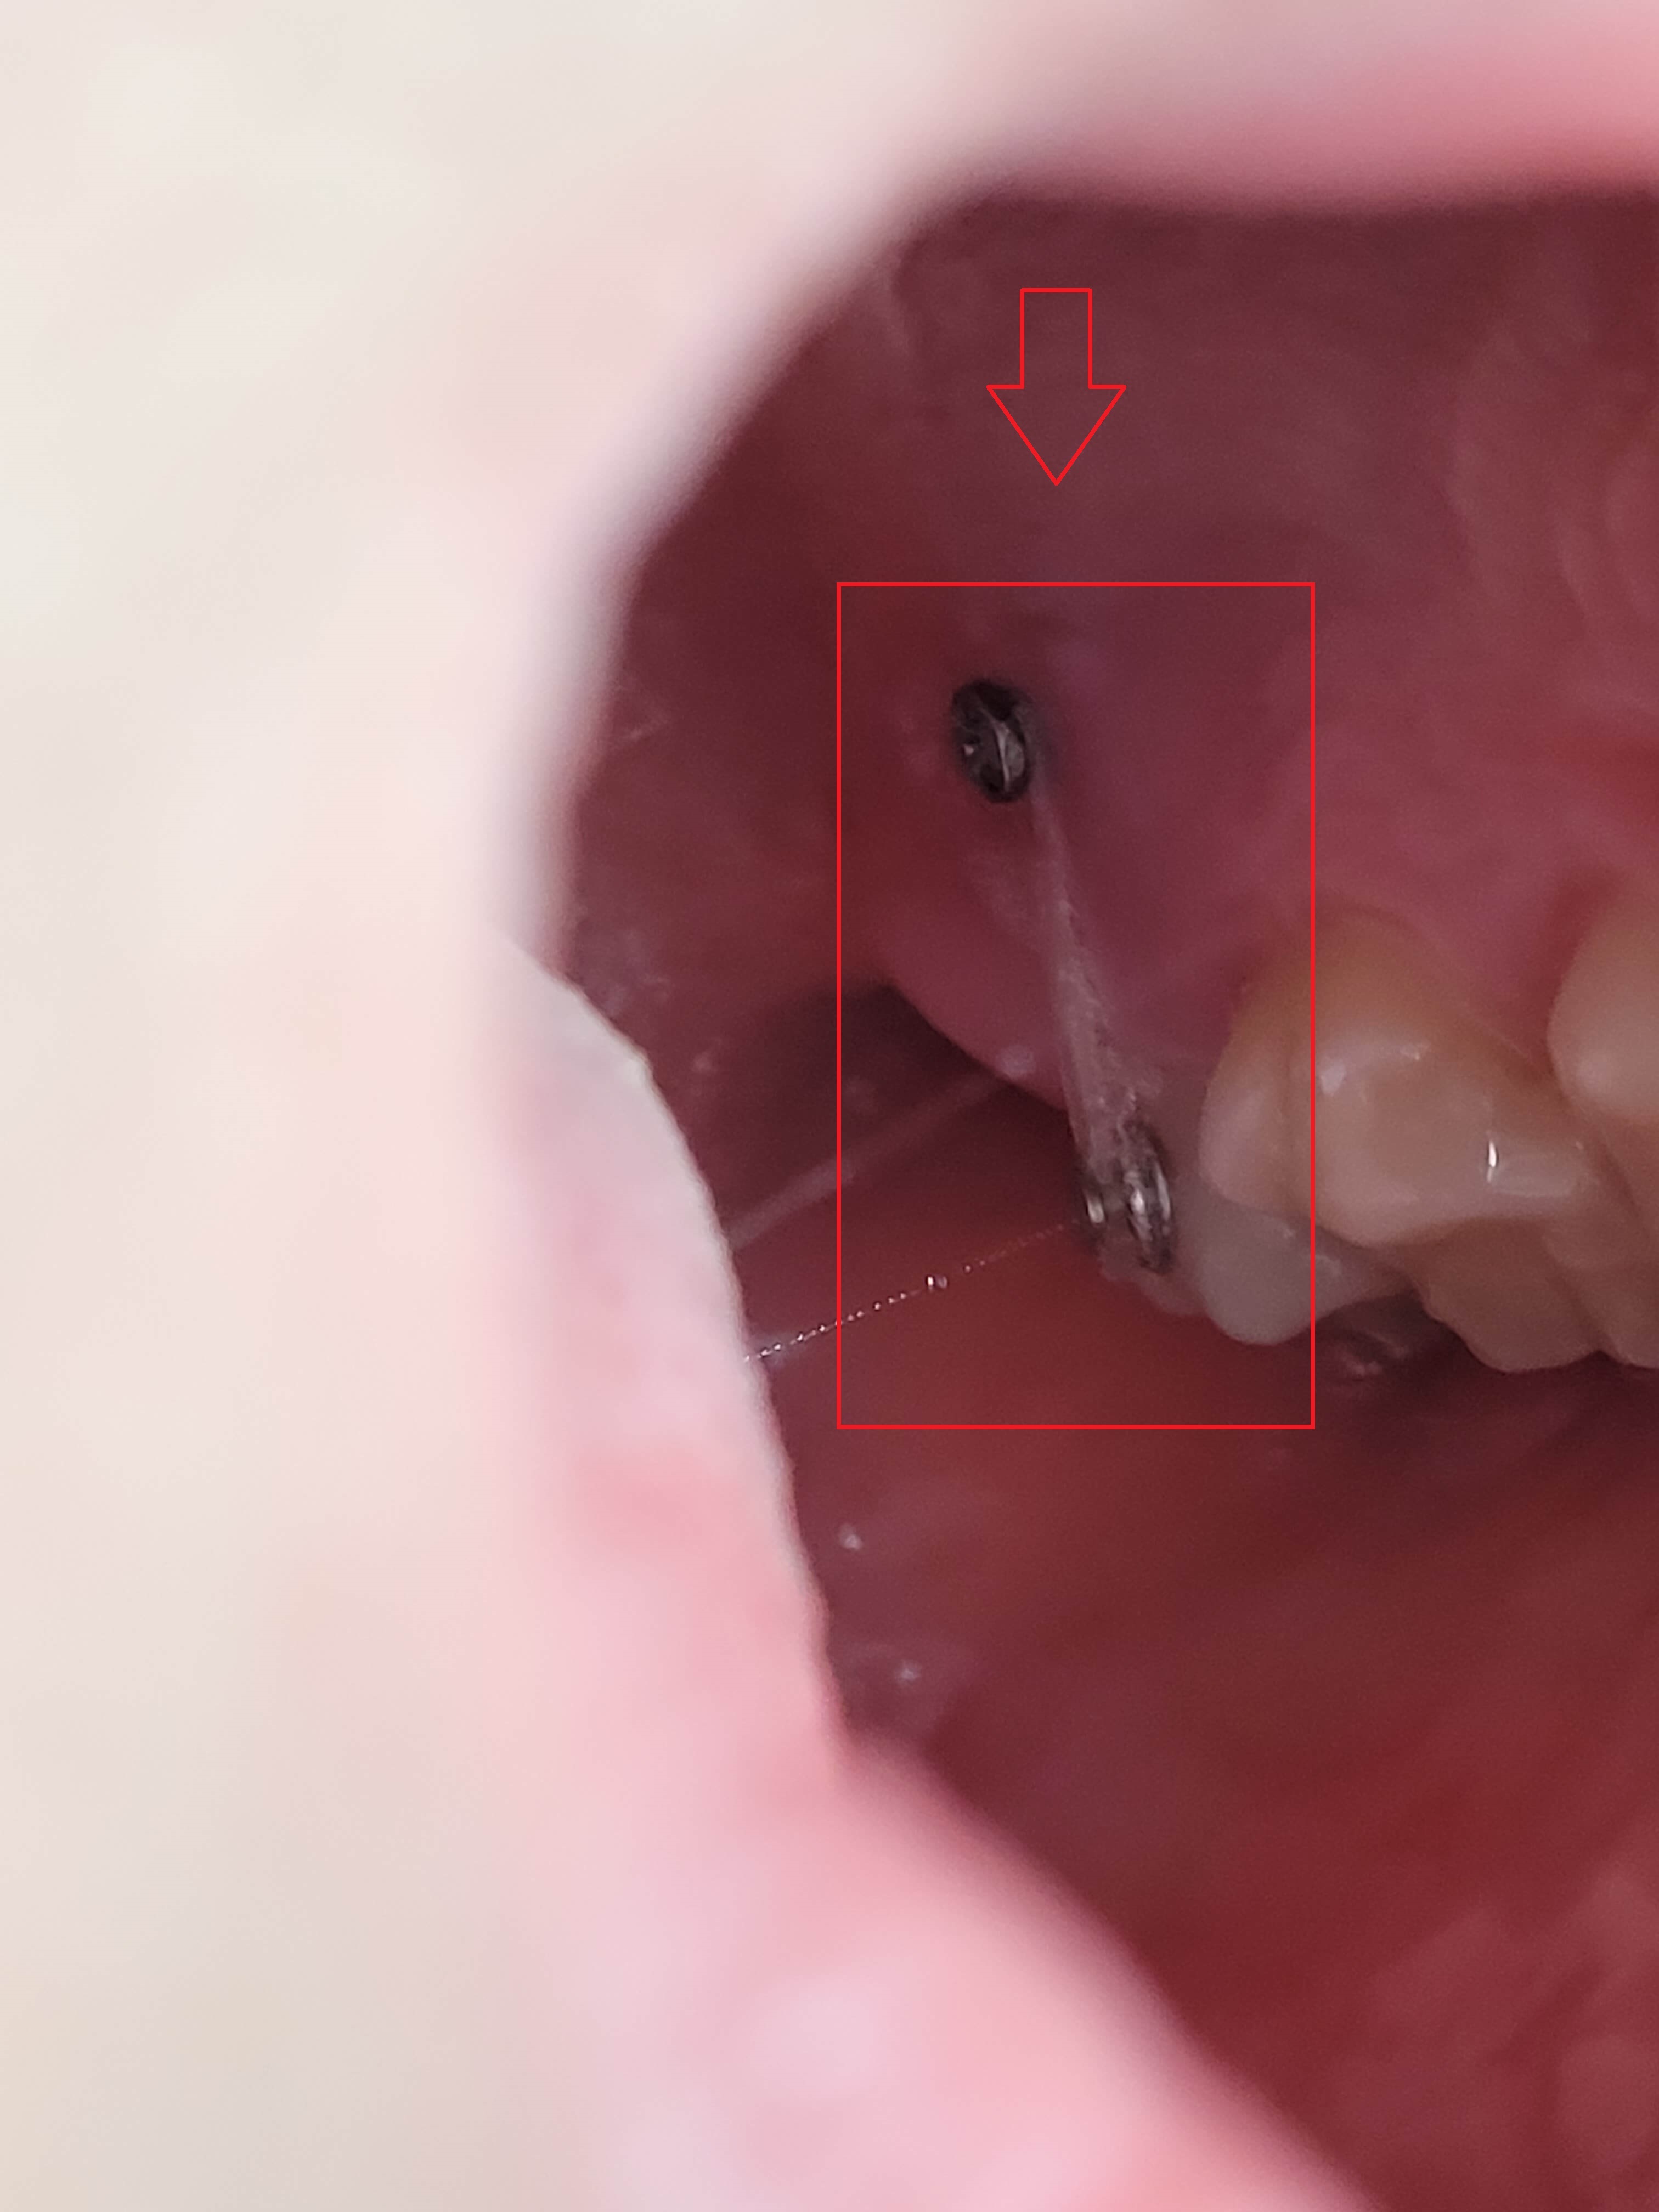

3. 가위교합 + 과개교합 교정실시 (전체브라켓 부착)

3개월간 가위교합 교정이 들어갔고 어느 정도 어금니가 제자리로 돌아왔습니다. 과개교합 교정을 위해 전체브라켓을 부착 하고 있는 사진입니다.

사진에 보면 철사가 S자 모양으로 휘어져 있습니다. 이 철사가 일자형으로 복원이 되면서 틀어진 치아배열을 정돈한다고 하는데 정확한 전문지식은 아니니 참고만 해주세요.

▼ 어금니 교정 후 전체 브라켓 부착